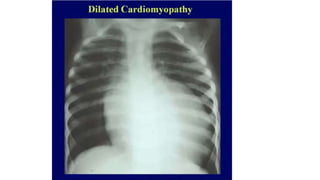

AorticCoarctation

• 5%–10% of congenital cardiac lesions

• Produced by a deformity of the aortic media and intima, which causes a

prominent

posterior infolding of the aortic lumen

• Occurs at or near the junction of the aortic arch and the descending thoracic

aorta

• Infolding cause eccentric narrowing of the lumen at the level where the

ductus or ligamentum arteriosus inserts anteromedially

• Resultant luminal narrowing in turn obstructs the flow of blood from

the left ventricle

• Classic radiologic signs

• Figure-of-three sign

• Reverse figure-of-three sign

Aortic Coarctation

Figureof Three,and Reverse Figureof Three

AorticCoarctation • 5%–10% ofcongenital cardiac lesions • Produced by a deformity of the aortic media and intima, which causes a prominent posterior infolding of the aortic lumen • Occurs at or near the junction of the aortic arch and the descending thoracic aorta • Infolding cause eccentric narrowing of the lumen at the level where the ductus or ligamentum arteriosus inserts anteromedially • Resultant luminal narrowing in turn obstructs the flow of blood from the left ventricle • Classic radiologic signs • Figure-of-three sign • Reverse figure-of-three sign